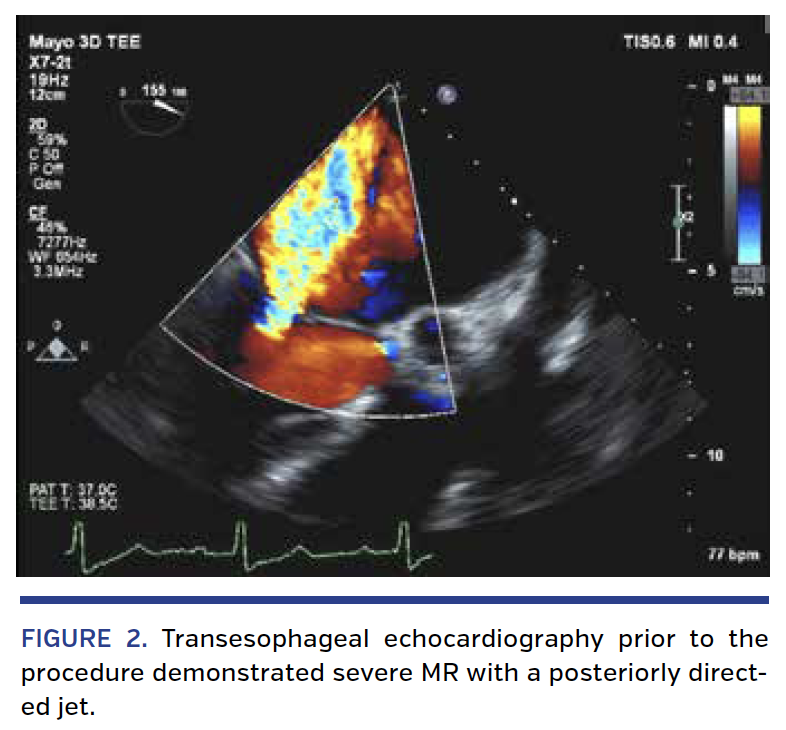

A 75-year-old man with a history of coronary bypass surgery presented with 3 weeks of fever. A transesophageal echocardiogram (TEE) revealed a 7 mm vegetation on the mitral valve with mild-moderate functional mitral regurgitation (MR) (Figure 1; Videos 1 and 2). After 4 weeks of antibiotics, he presented with New York Heart Association class III dyspnea and repeat TEE demonstrated severe MR (Figure 2; Videos 3 and 4) with the anterior leaflet thickened and retracted with resultant malcoaptation (Videos 5 and 6). Magnetic resonance imaging of the brain showed 2 acute lacunar infarcts. On hospital day 3, he developed profound dyspnea with hypotension and acute renal failure. The patient remained dyspneic and anuric despite maximal medical support. Dialysis was initiated. Surgery was considered prohibitive due to multiple comorbidities. After consultation with Infectious Diseases, it was determined the infection risk was low and transcatheter mitral valve repair (TMVR) was offered.